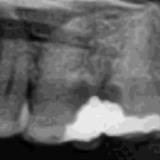

Immediate Implant Placement

A molar either maxillary or mandible always represents a little difficult and tricky scenario for implant placement immediately after extarction. There is always some sacrifice for the location, angle etc. however you save some time and patients go through a procedure once and it is a reliable method of replacing a tooth, when feasible. Dental implant is always a compromised replacement and a tooth restored with immediate placement is not any different.